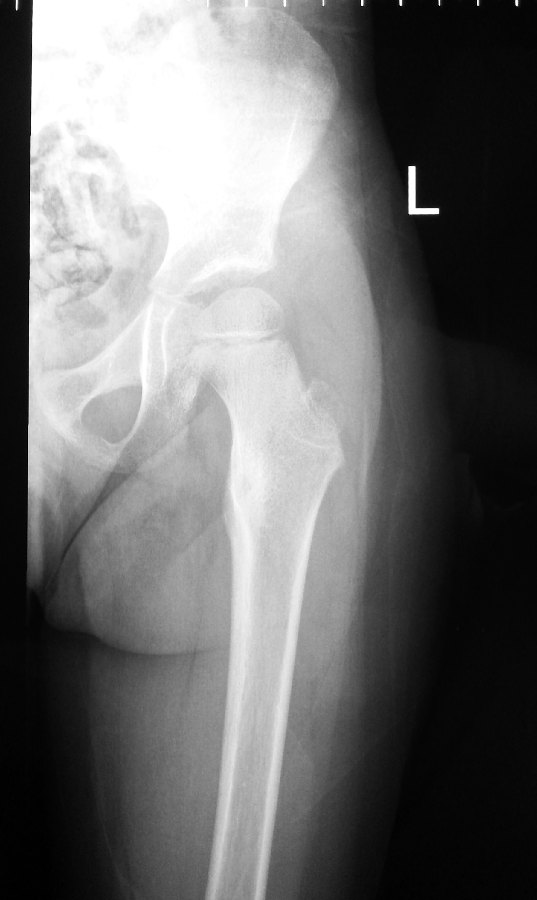

I ordered an x-ray of her pelvis and left thigh (femur bone).

The x-rays of her pelvis allowed me to compare the hip joints of both the right and left sides.

It clearly showed increased sclerosis (thicker bone) in the left hip around the lesser trochanter.

The arrow shows the area of increased whiteness or sclerosis of the bone from a possible osteoid osteoma.

The x-rays were suggestive of a condition called Osteoid Osteoma.

A CT-scan was immediately ordered to confirm the diagnosis.